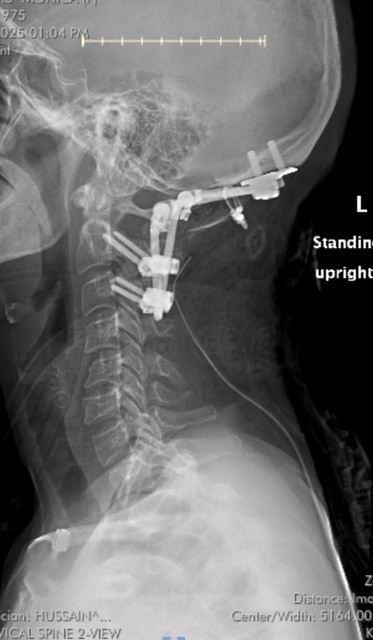

For me, that disruption arrived through my body. After years of dismissal and misdiagnosis, I finally learned what had been unraveling me from the inside out: Craniocervical Instability (CCI), Chiari Malformation, and Hypermobile Ehlers-Danlos Syndrome (hEDS). What began as symptoms no one thought to connect eventually had names. That was the beginning of a different kind of work.